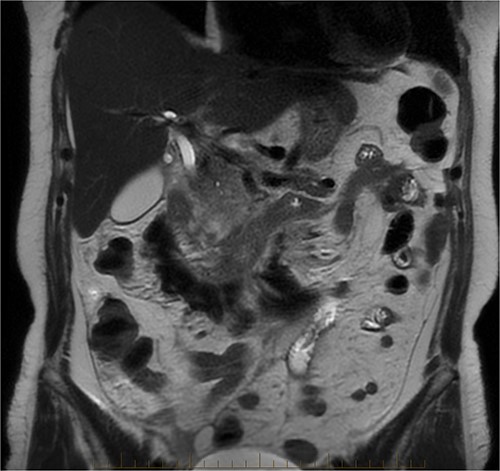

The radiologist suggested a computer tomography (CT) scan to further explore the potential causes for this fluid. The CT abdomen and pelvis revealed extensive oedema and induration surrounding the duodenum with a complex hyperdense fluid, extending from this site to the paracolic gutters and into the pelvis. While these findings are suspicious of a paraduodenal hemorrhage from a ruptured duodenal ulcer and hemoperitoneum, they were not typical for perforated duodenal ulcer or erosion into the blood vessels. Differentials were an infiltrating mass either fibrotic or of a lymphoproliferative origin. However, this could not explain the complex fluid in the abdomen (Figs 1 and 2).

CT abdomen, coronal view. Hyperdense fluid centered around the duodenum and tracking into the paracolic gutters. Appearance concerning for paraduodenal hemorrhage, infiltrating mass was considered less likely.